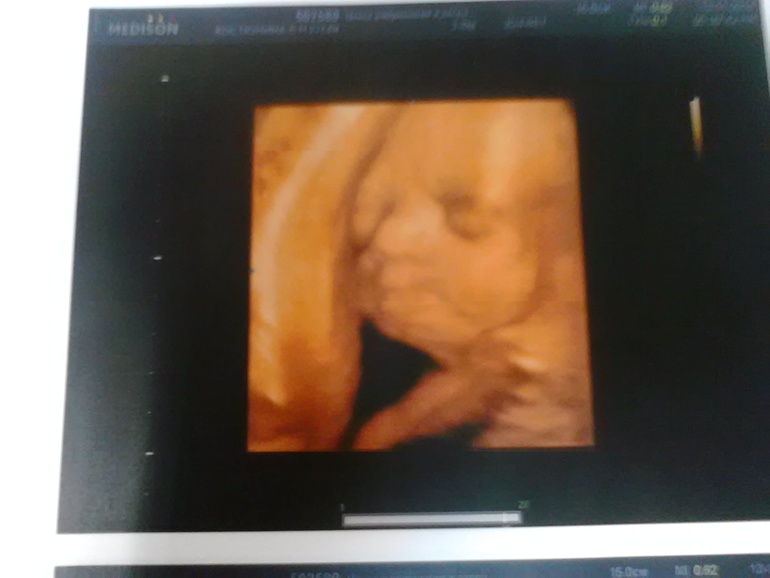

такие фото хорошие) тоже побаиваюсь декрета и именно в финансовом плане) может какую пока халтурку поискать?А еще вопрос к вам? вы почему так рано узи сделали? просто так сами или назначили?

да я сама виновата, у нас организация нестабильная, все непонятно, никто нормально объяснить не может, а на УЗИ в платную сходила чисто из интереса